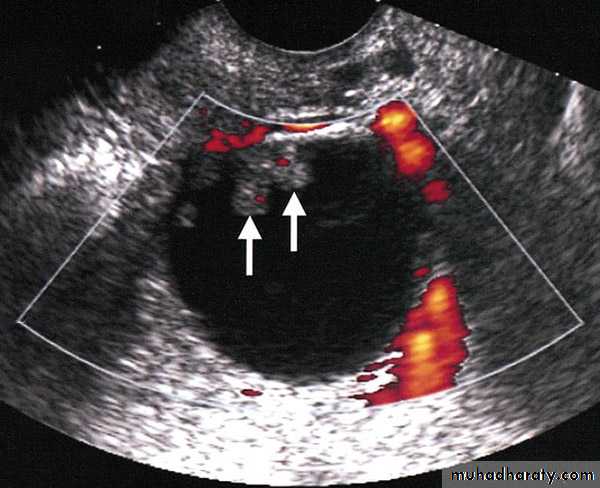

The patient have 2 miss period, she have positive B.HCG presented as acute abd. Laproscopy done for her, what is the finding?Out line the treatment options?